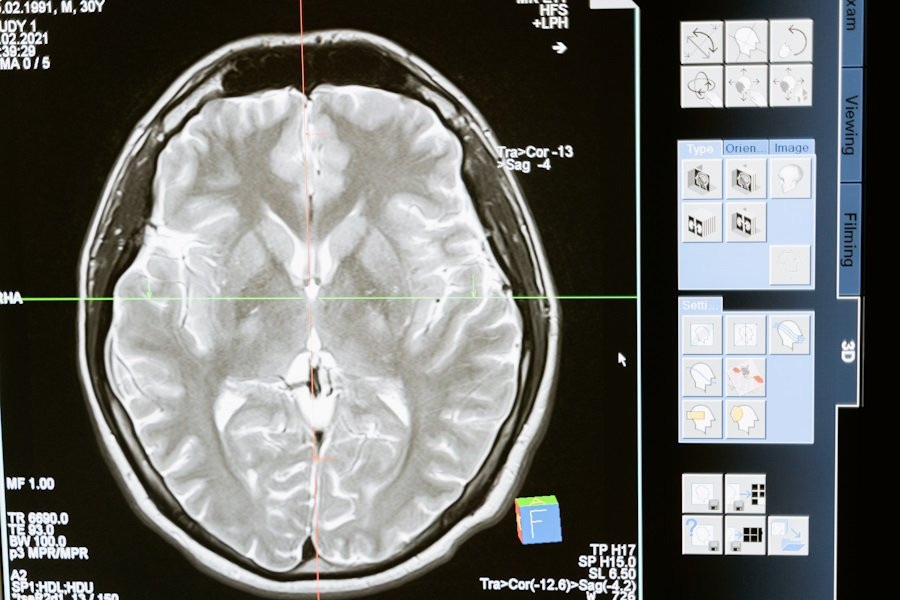

Российские ученые смогли победить рак головного мозга

Нейрофизиологи ИВНД РАН представили уникальную технологию, которая обещает революционизировать лечение глиобластомы головного мозга - одной из наиболее агрессивных форм рака, сообщает издание "РГ".